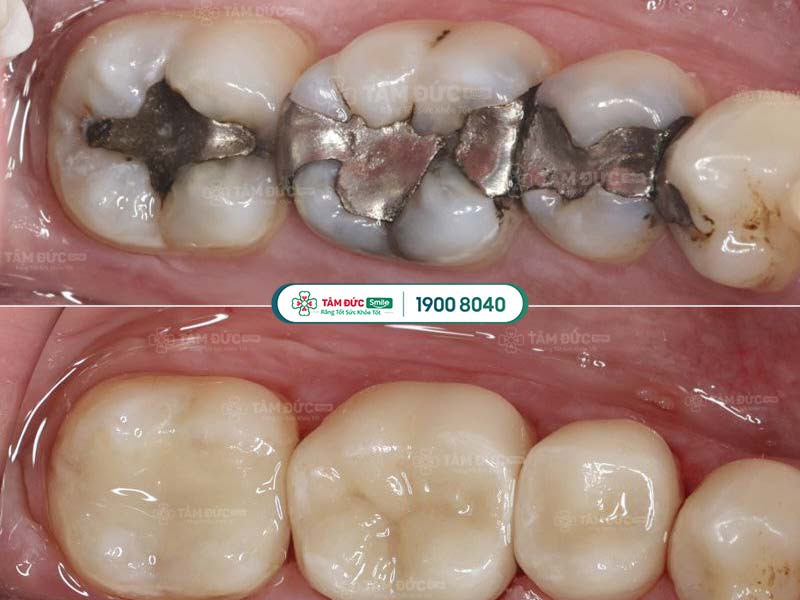

1.4. Thay miếng trám mới

Hiệu quả trám răng không thể duy trì vĩnh viễn. Theo thời gian, miếng trám răng cũ có thể bị bong tróc hoặc rơi ra do tác động từ lực ăn nhai. Trong trường hợp này, bác sĩ sẽ yêu cầu thay miếng trám răng mới.

răng trám cũ và răng trám mới

Quý khách cần trám lại răng khi miếng trám cũ bị bong tróc